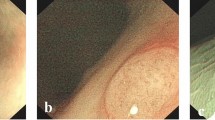

The deep learning-based classification model typically consists of the feature extractor and the classifier. Such models are often difficult to understand. On the one hand, the extracted features are not interpretable in clinical practice. On the other hand, due to the errors of the classifier, there is a certain perturbation between the features and the final classification prediction, which means good features do not necessarily represent correct prediction results. Regarding the uninterpretability of extracted features in clinical practice, we employed the Gradient-weighted Class Activation Mapping (Grad-CAM) method to generate class activation mapping, which regions of image features play a key role in determining a particular category output of the features from different layers of our model (Fig. 6a). From this, we can see that the model mainly focuses on the blood vessels, which is consistent with our clinical knowledge. Further, we also output all the class activation mappings of each transformer block in our model, and we can see that with the deepening of the blocks, the model’s region of interest gradually converges to the vascular area in the EC images (see Fig. S1 in the Supplementary Information File). By perturb the labels, we can see that the model’s class activation mappings are also changed, thus: λfor the non-neoplastic category, the model mainly focuses on the fuzzy and unclear margin microvessels of the image; for the adenomas category, the model primarily focuses on the dense, regular and clear margin micronetworks in the EC images; and for the invasive cancer category, the model mainly focuses on the irregular, thick and sparse microvessels in the EC images. (see Fig. S2 in the Supplementary Information File).

It is well known that EC offers the highest magnification among endoscopic imaging modalities, holding significant potential for achieving ‘optical biopsy’. From non-neoplastic lesions to adenomas and invasive cancers, the microvessels become increasingly thicker and irregular with an increasing grade of lesion dysplasia (Fig. 6a). The precise real-time endoscopic diagnosis of colorectal lesions is critical for endoscopists in selecting appropriate treatment strategies. However, it is difficult for endoscopists, especially novice endoscopists, to make accurate diagnoses using EC-NBI. To address this issue, we collected approximately 480,000 publicly available endoscopic images to pre-train the foundation of the large model. Then, we collected 8615 EC-NBI images (from 315 patients) at the First Hospital of Jilin University to conduct in-domain CPT and SFT of the model. Ultimately, we have successfully developed a computer-aided diagnosis model based on EC-NBI for predicting the classification of colorectal lesions. In contrast to previous machine learning-based binary classification CAD models, our model effectively discriminated non-neoplastic lesions, adenomas, and invasive cancers, which can be integrated into the clinical workflow to provide real-time assistance for disease diagnosis (An example of real-time diagnosis in the Supplementary Movie 1). By rapidly determining lesion pathology, endoscopists optimize treatment strategies, enhancing clinical outcomes.